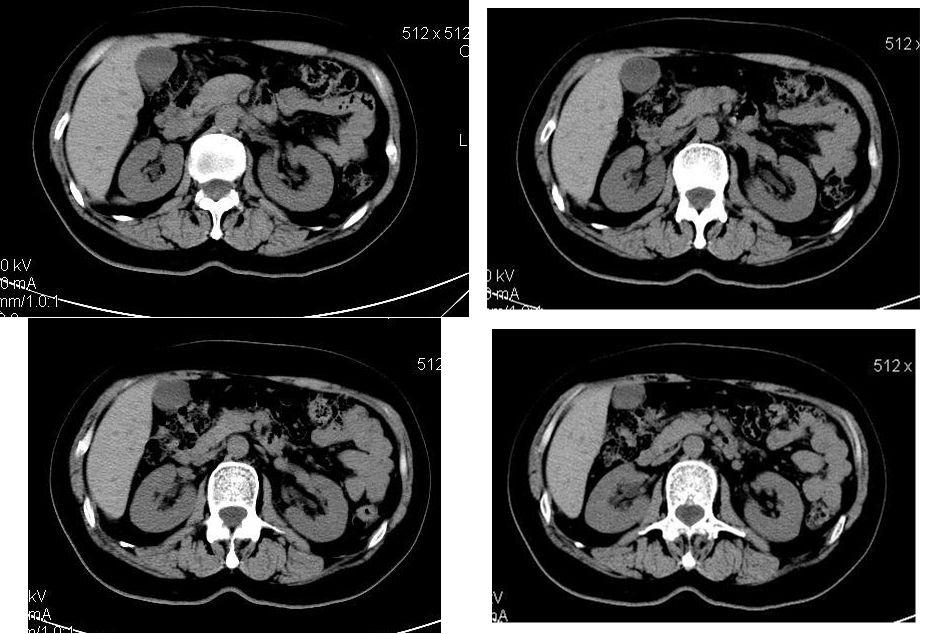

延迟扫描

肝左叶内侧段肝癌,肝右叶可见小结节灶,并见强化,考虑转移.

学习了,这可能是脂肪含量少的血管平滑肌脂肪瘤,因血管丰富所以动脉期密度升高明显,但该患无肝硬化表现,所以,诊断肝癌,依据不足.谢谢上传.对今后工作是一个提醒.